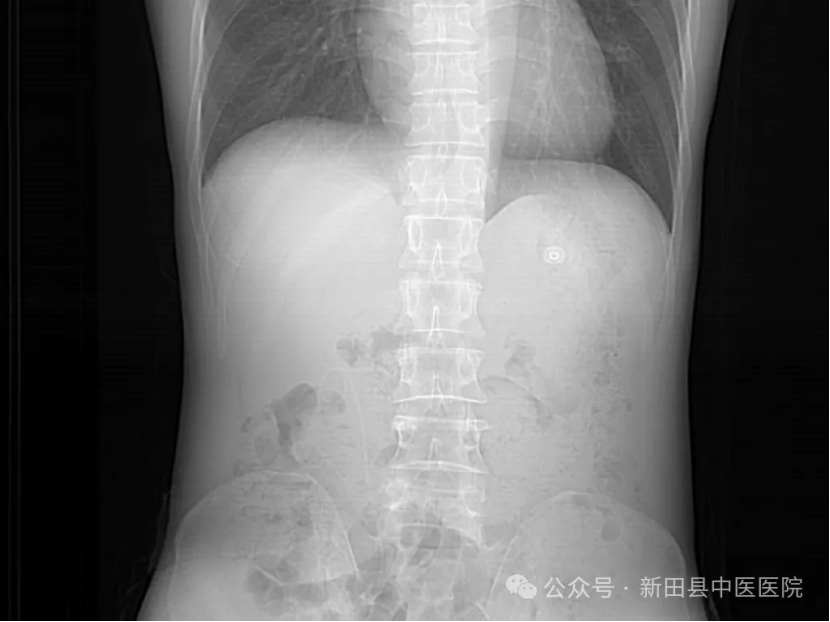

术后影像学检查提示,右肾结石清除干净。一周后,陈女士康复出院时,对邓勇军主任连声称赞。

▲术后DR